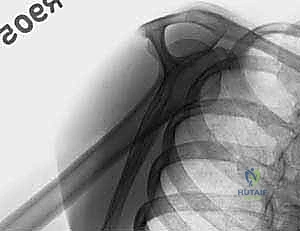

- الأشعة السينية (X-rays): يتم أخذ صور من زوايا متعددة (أمامية خلفية، جانبية، وإبطية) لتحديد نوع الكسر وموقعه.

2. التصوير الشعاعي اللحظي (C-arm)

يتم استخدام جهاز الأشعة المرئية (Fluoroscopy) طوال فترة العملية لضمان الرؤية الدقيقة للكسر ومسار الأسلاك دون الحاجة لفتح الجلد.

3. الرد المغلق للكسر (Closed Reduction)

بمهارة يدوية فائقة، يقوم الدكتور هطيف بإعادة الشظايا العظمية إلى مكانها التشريحي الصحيح عن طريق سحب الذراع وتدويرها بآليات محددة، كل ذلك تحت مراقبة الأشعة.